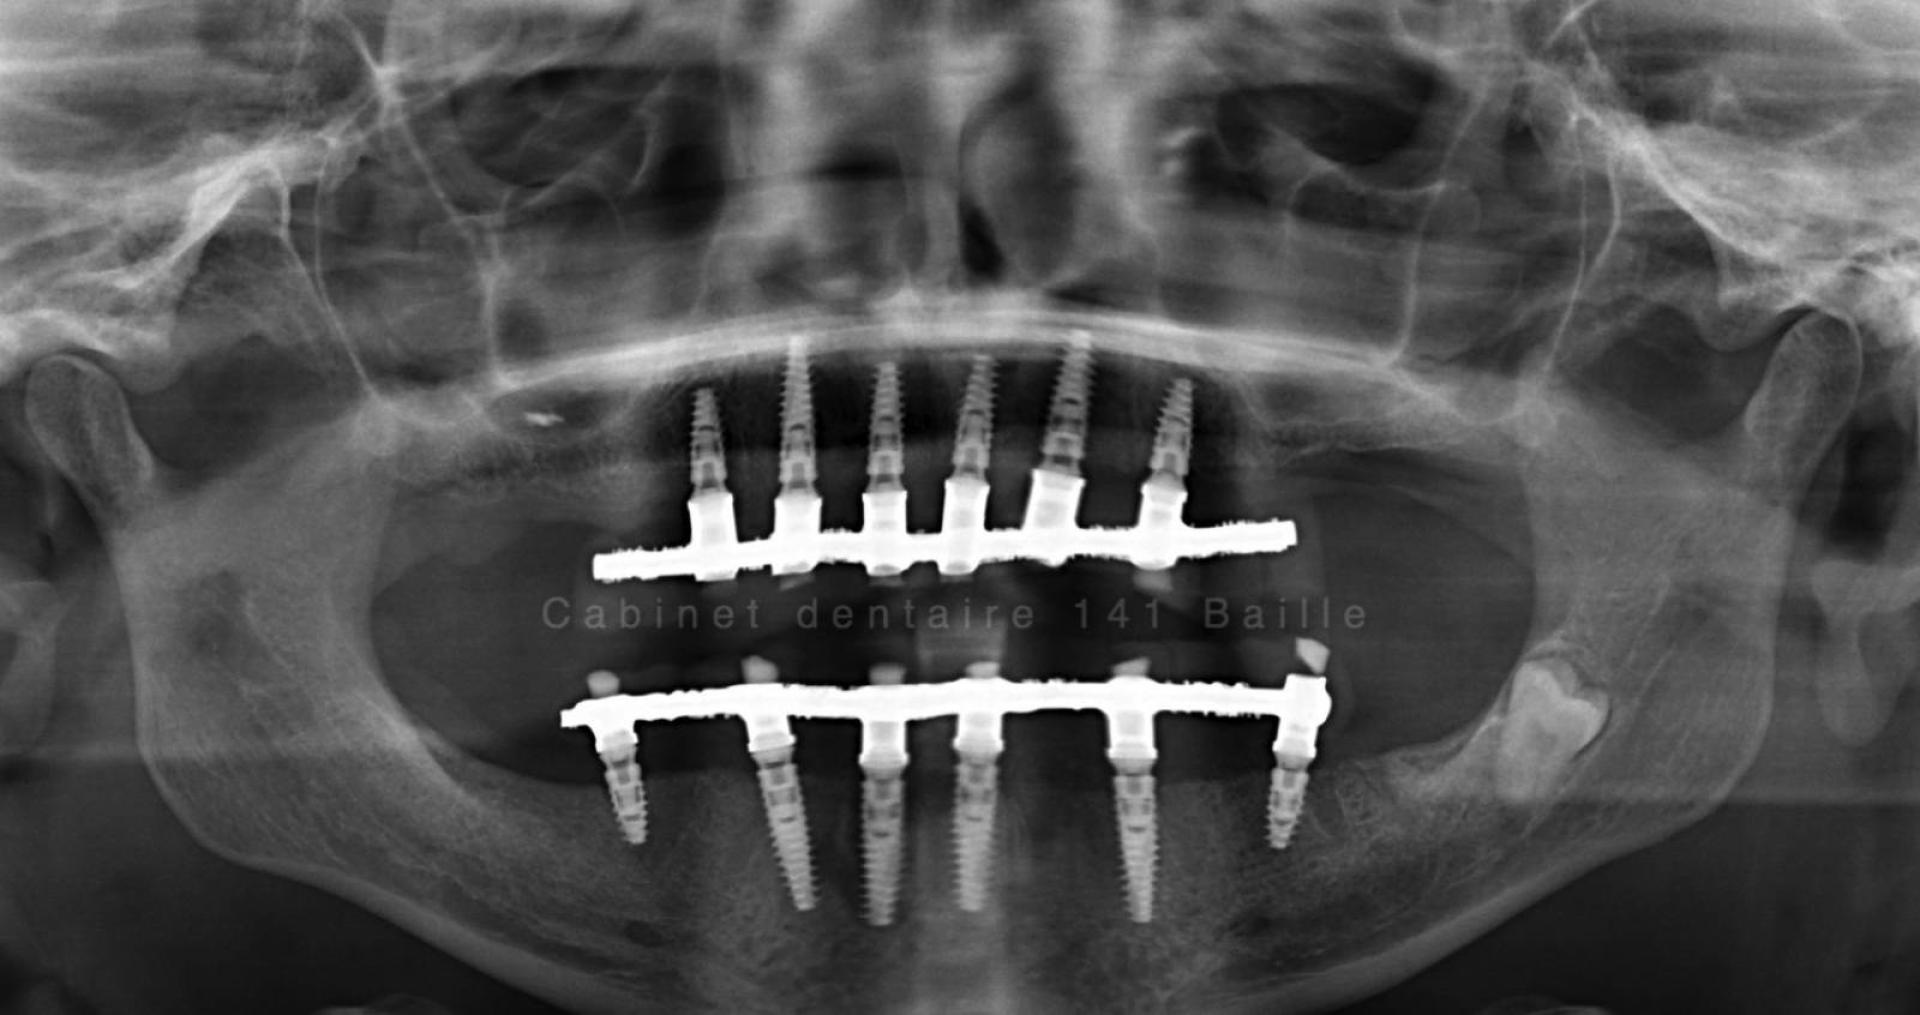

Techniques de mise en charge immédiate des implants à Marseille Cabinet 141 Baille

Le jour de l'intervention tous les implants seront mises en place les Greffes osseuses seront effectuées ,les piliers implantaires  seront connectés et une prothèse complète sera réalisée le jour même et vissé sur les implants.